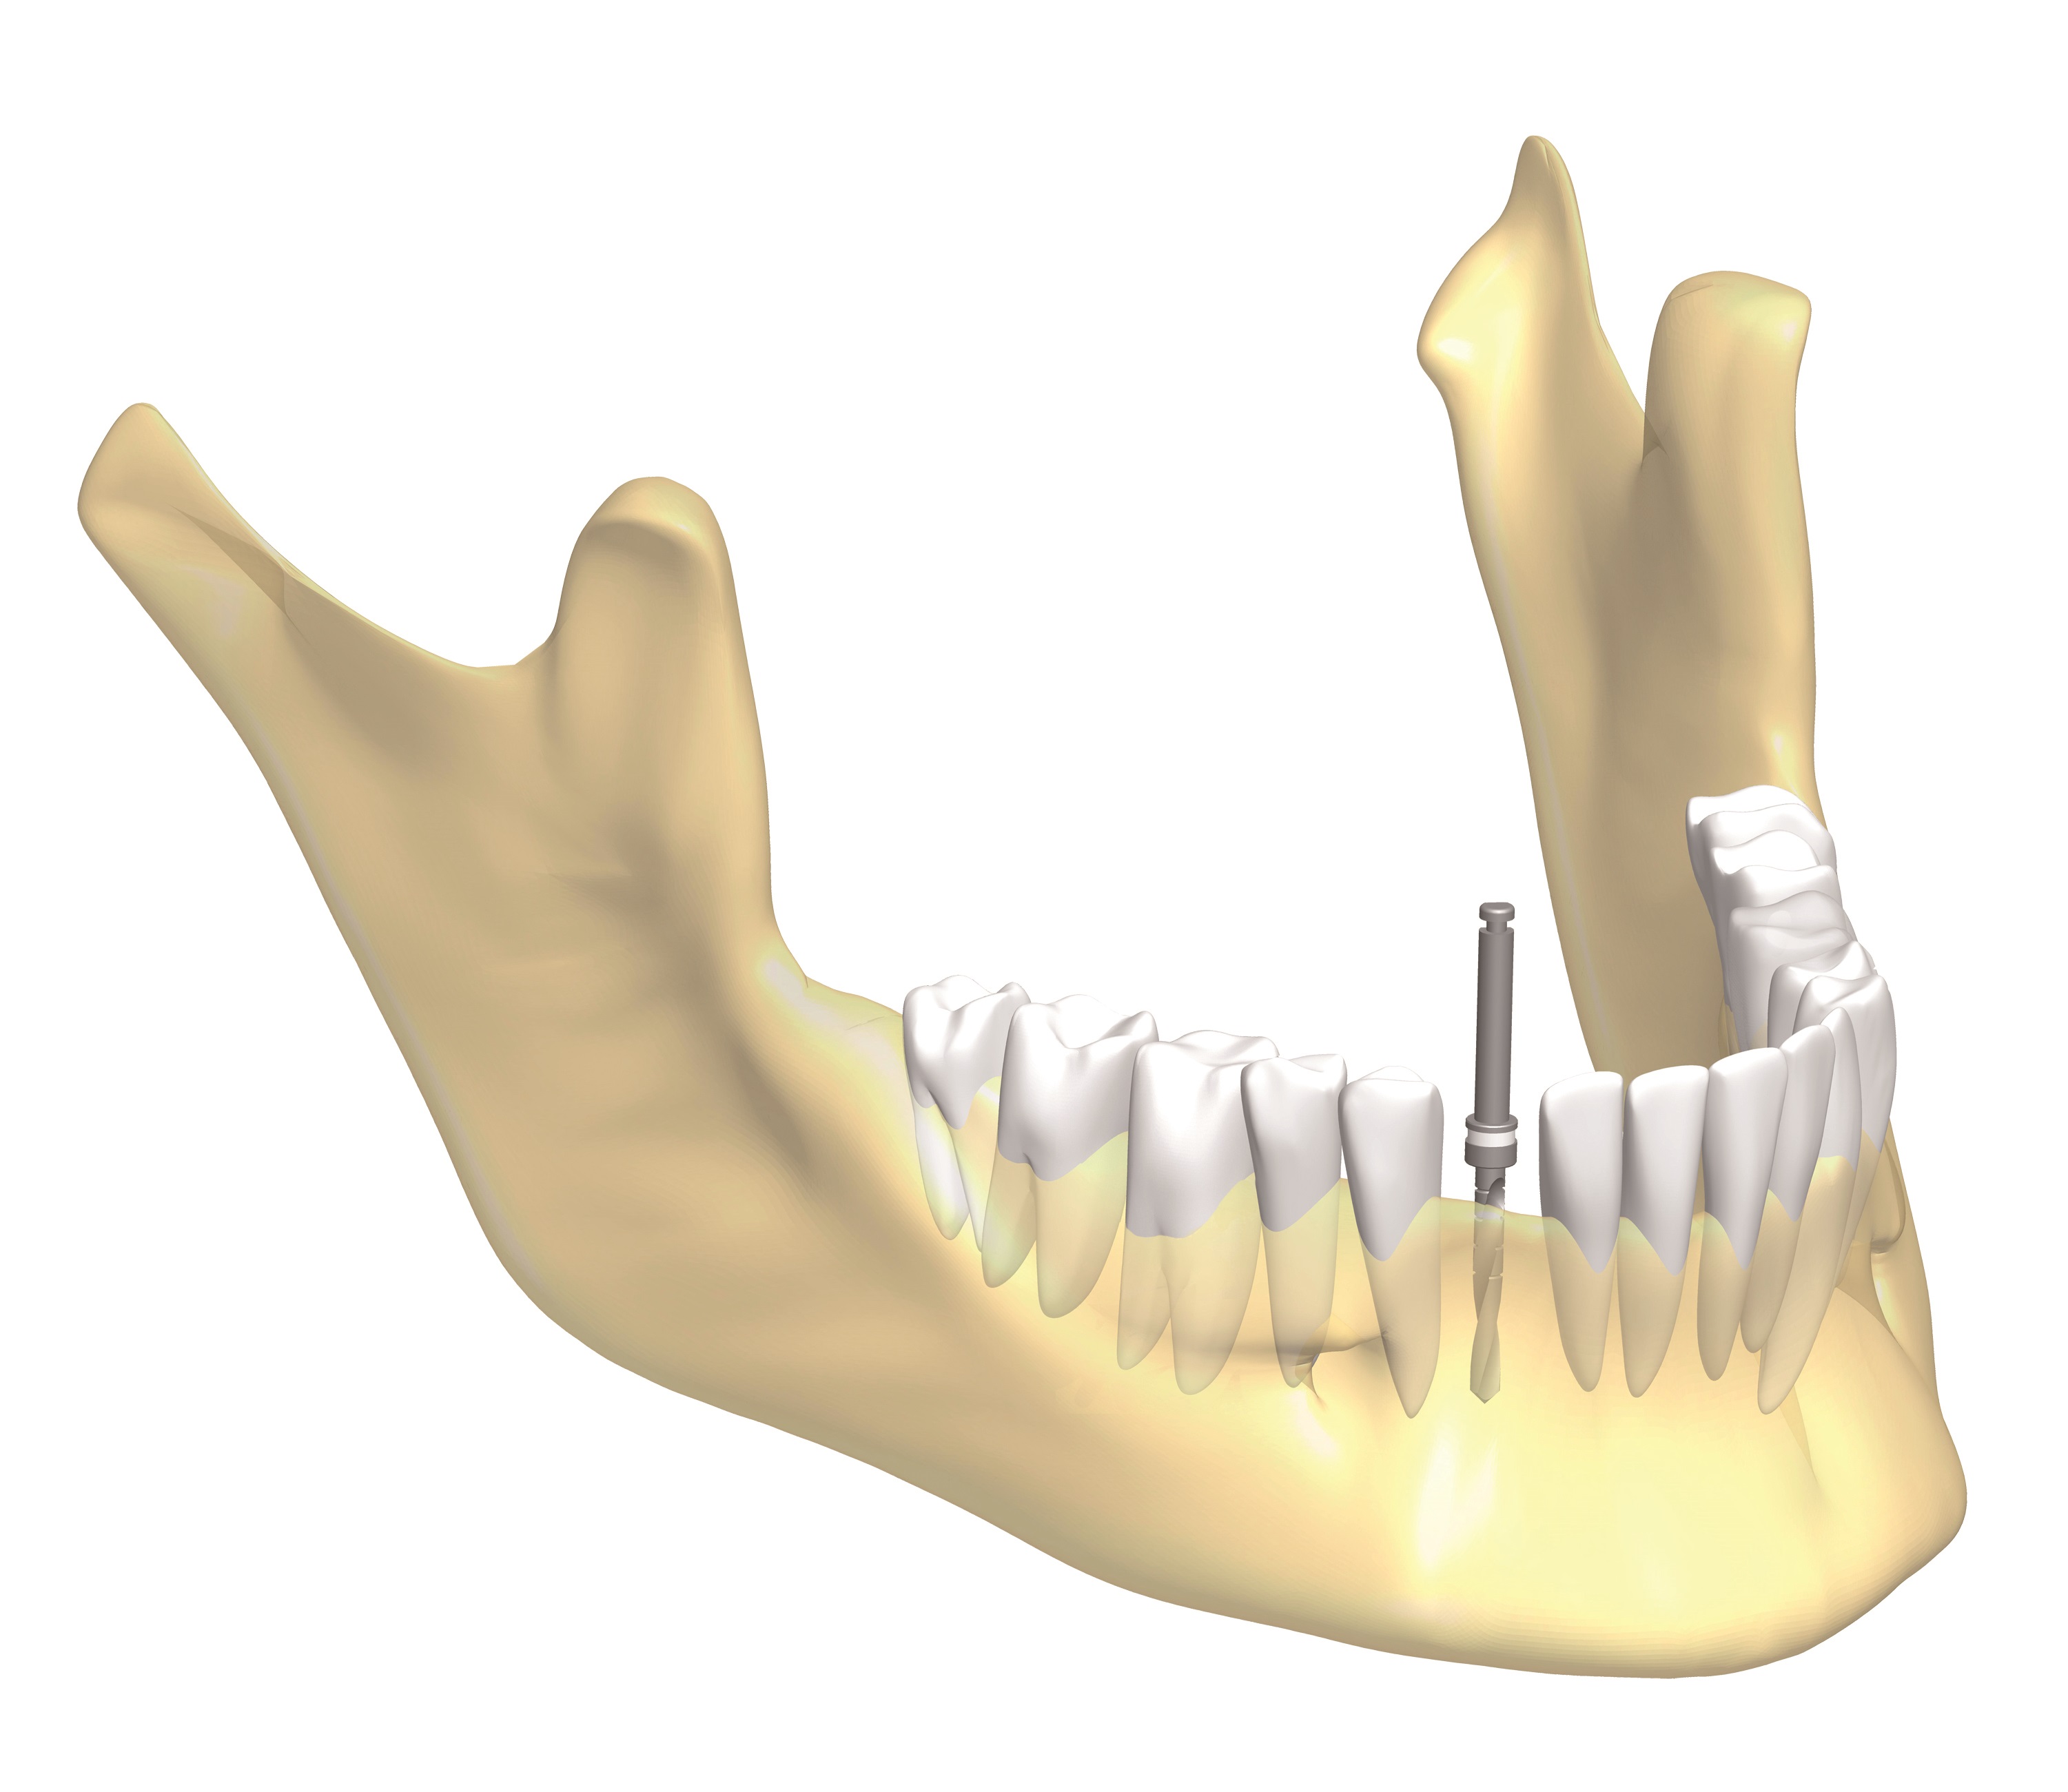

1. Előzetes vizsgálatok alkalmával a kezelőorvos röntgen és CT felvételek alapján felméri a implantátum pontos helyét, a rendelkezésre álló csont mennyiségét, minőségét, az implantátum szomszédos fogaktól való távolságát és az implantátumra kerülő fogpótlás tervezett elhelyezkedését.

2. Helyi érzéstelenítést követően a nyálkahártyát az orvos leválasztja a csontról, majd a megfelelő méretű speciális fúróval furatot készít a csontban.